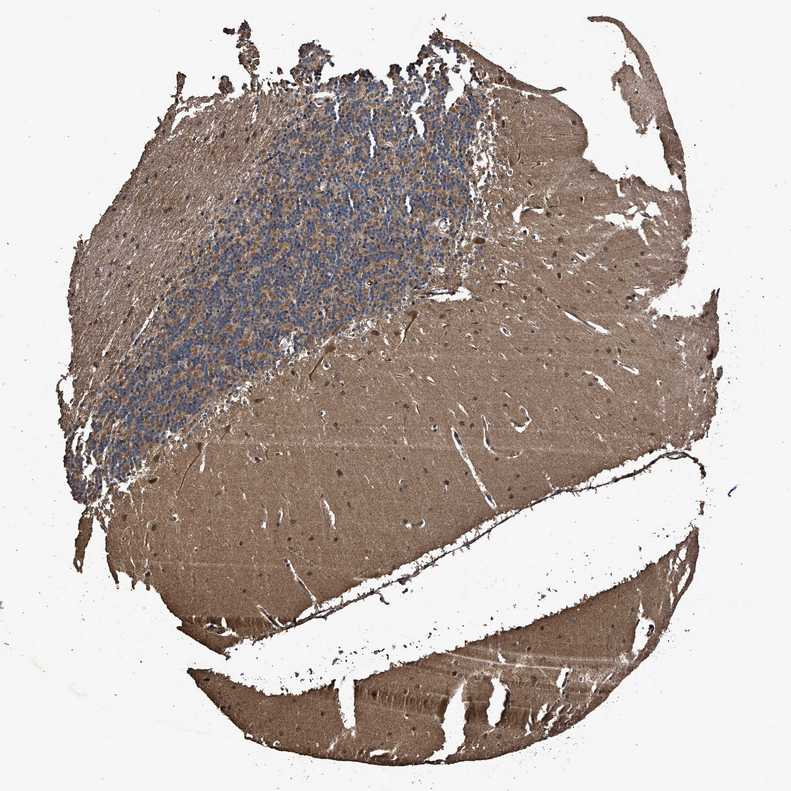

BRAIN CEREBELLUM Show tissue menu

CEREBELLUM - Expression summary

CEREBELLUM - Antibody stainingi

Antibody staining in the annotated cell types in the current human tissue is reported as not detected, low, medium, or high, based on conventional immunohistochemistry profiling in selected tissues. This score is based on the combination of the staining intensity and fraction of stained cells.

Each image is clickable and will lead to virtual microscopy that enables deeper exploration of all samples and also displays staining intensity scores, fraction scores and subcellular localization as well as patient and tissue information for each sample.

Antibody HPA020642Antibody HPA050761

Purkinje cells HighLow

Cells in granular layer MediumMedium

Cells in molecular layer MediumLow